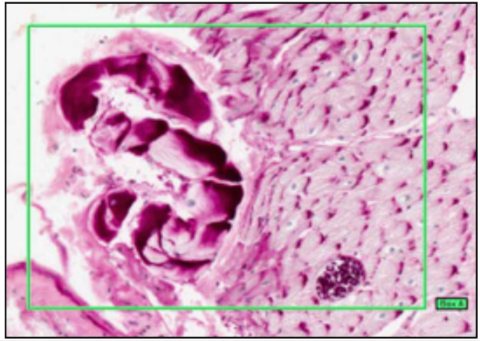

ARTERY WITH PLAQUE AND THROMBUS (WITH IRON HAEMATOXYLIN)

- elastic/nucleus = black